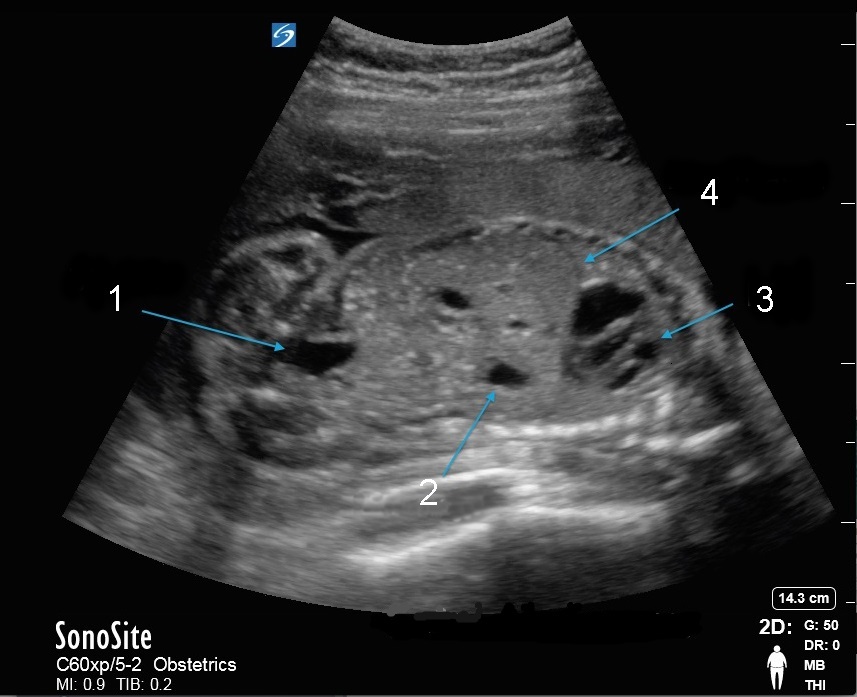

Imagen pélvica de abdomen fetal

Vejiga

Estómago

Terapia de reemplazo hormonal (TRH)

Diafragma